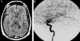

Extradural arteriovenous fistula